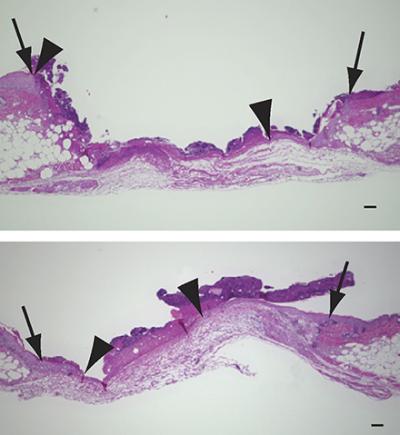

Researchers from Japan were prompted to investigate the role of a molecule called 12-HHT and its receptor BLT2 in wound healing; 12-HHT is produced during blood coagulation following skin injury and BLT2 is found on the surface of keratinocytes. The researchers showed that 12-HHT promotes the re-formation of the epithelial layer at wound sites by enhancing the migration of keratinocytes. They discovered that high dose aspirin, the most commonly used nonsteroidal anti-inflammatory drug, delays wound healing by reducing the production of 12-HHT. The researchers also found that a synthetic mimic of BLT2 accelerated wound healing in diabetic mice (a model that is commonly used to investigate delayed wound healing).